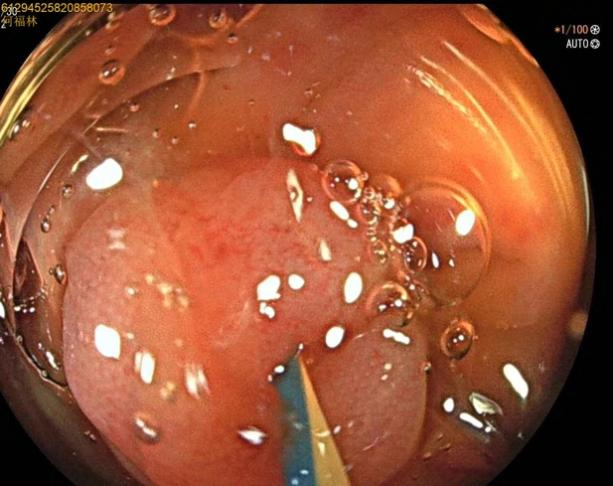

52岁,女性患者,主因“反复右下腹痛1年,再发2天”入院,既往有急性阑尾炎发作病史,入院腹部查体:右下腹麦氏点明显压痛,无肌紧张及反跳痛;完善腹部+盆腔CT示:阑尾管腔增粗并阑尾粪石形成,周围多发淋巴结显示。结合患者的病史及检查考虑慢性阑尾炎急性发作。次日,行肠镜检查,进至阑尾口,置入子镜(洞察内镜)进入阑尾,见阑尾黏膜充血、水肿,附着有白色絮状分泌物,确诊急性阑尾炎发作,进一步行内镜下逆行性阑尾治疗术,术中给予阑尾腔冲洗后植入塑料支架,术后患者腹痛即可缓解。